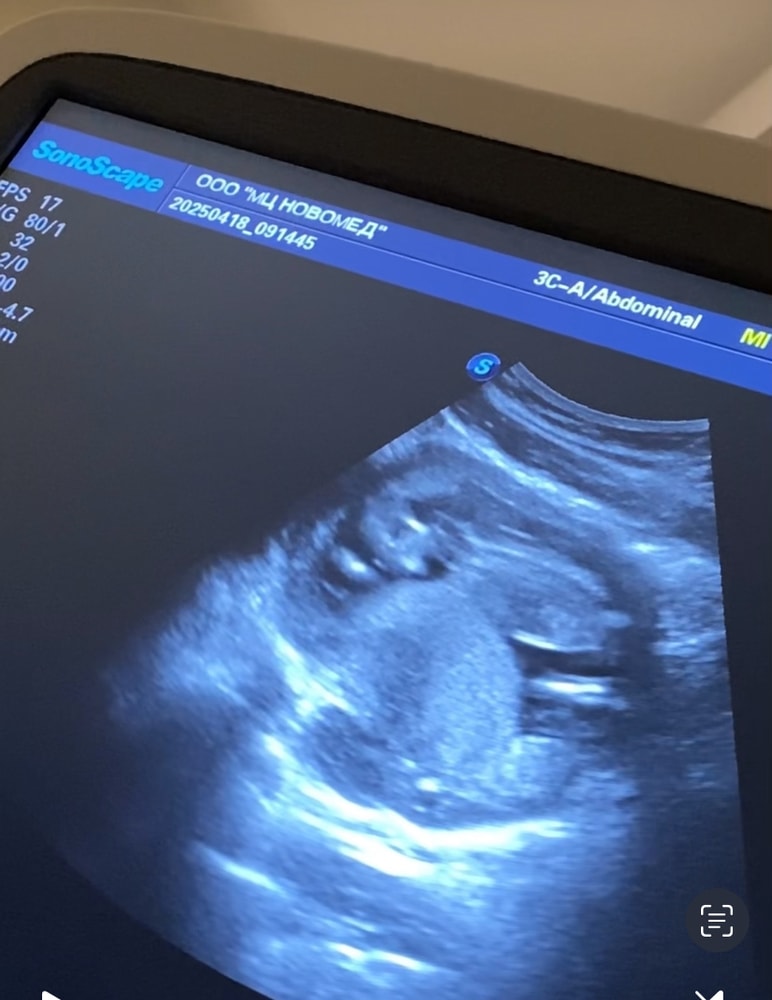

13,6 недель моему малышу ❤️

18.04.2025